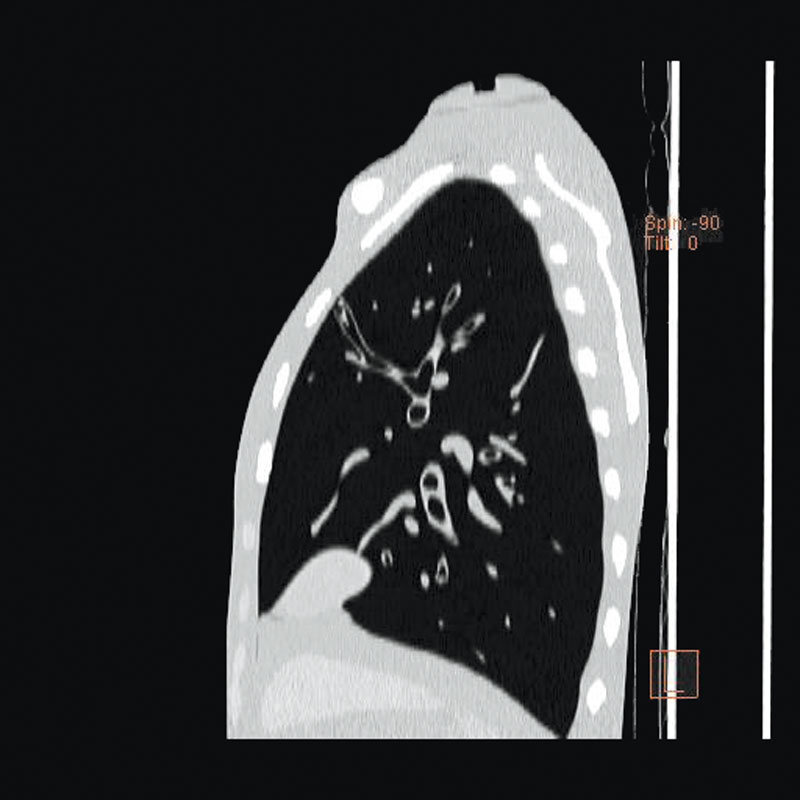

Ein einzigartiges Ganzkörperphantom für CT bietet eine Vielzahl von Ausbildungs- und Forschungsmöglichkeiten. Das Phantom kann auch für normales Röntgen benutzt werden und gibt lebensnahe Bilder. Es benden sich keine Metallteile oder Flüssigkeiten im Phantom. Die wichtigen Gelenke haben eine menschenähnliche Beweglichkeit und erlauben vielfältige Positionen für die Übung. Das Phantom kann in 10 Teile zerlegt werden. Die verbesserten Schultergelenke erlauben es, die Arme nach oben zu bewegen. Die künstlichen Organe sind anatomisch korrekt und haben entsprechende HU-Zahlen.

- Lungen mit Pulmonalgefäßen

- Luftröhre

Radiologische Absorption und Hounsfield-Nummer ähnlich dem menschlichen Körper.